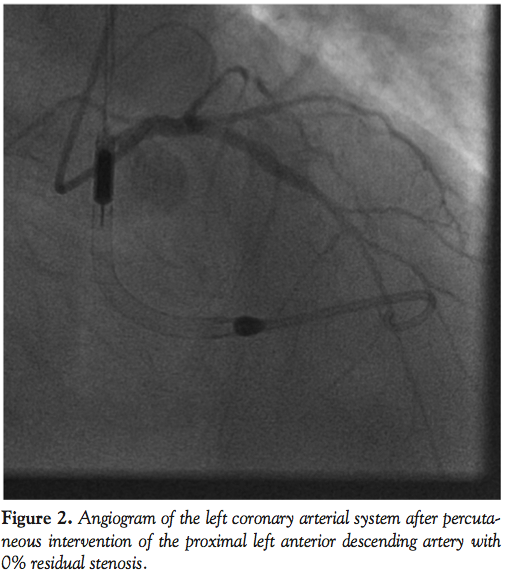

A 79-year-old male with known coronary artery disease presented with congestive heart failure as well as 1 month of progressive epigastric pain. His initial electrocardiogram showed LVH and cardiac biomarkers were within normal limits. An echocardiogram demonstrated severe LV dysfunction with an estimated ejection fraction of 25%. Diagnostic angiography revealed a severe stenosis in the LAD (Figure 1). Given the degree of LV dysfunction, the decision was made to proceed to PCI of the LAD lesion with percutaneous hemodynamic support. Right femoral artery access was obtained and a 13 Fr sheath was placed into the artery after serial dilations. Anticoagulation was given with intravenous heparin. An Impella 2.5 device was placed into the LV in a retrograde fashion and provided 2.5 L/min of cardiac output support. A 6 Fr Glidesheath was placed in the right radial artery, through which a 6 Fr XB LAD 3.5 guide catheter (Cordis Corporation) was used to engage the left main coronary ostium. Intervention was performed with two drug-eluting stents placed in overlapping fashion with a reduction in stenosis from 80% to 0% with TIMI-3 flow (Figure 2). After the procedure, the right femoral artery sheath was removed with closure of the arteriotomy performed using two Perclose Proglide closure devices. The radial artery sheath was removed and a pneumatic compression device was used for hemostasis. The patient was transferred to the cardiac care unit for monitoring. There were no bleeding or vascular complications.